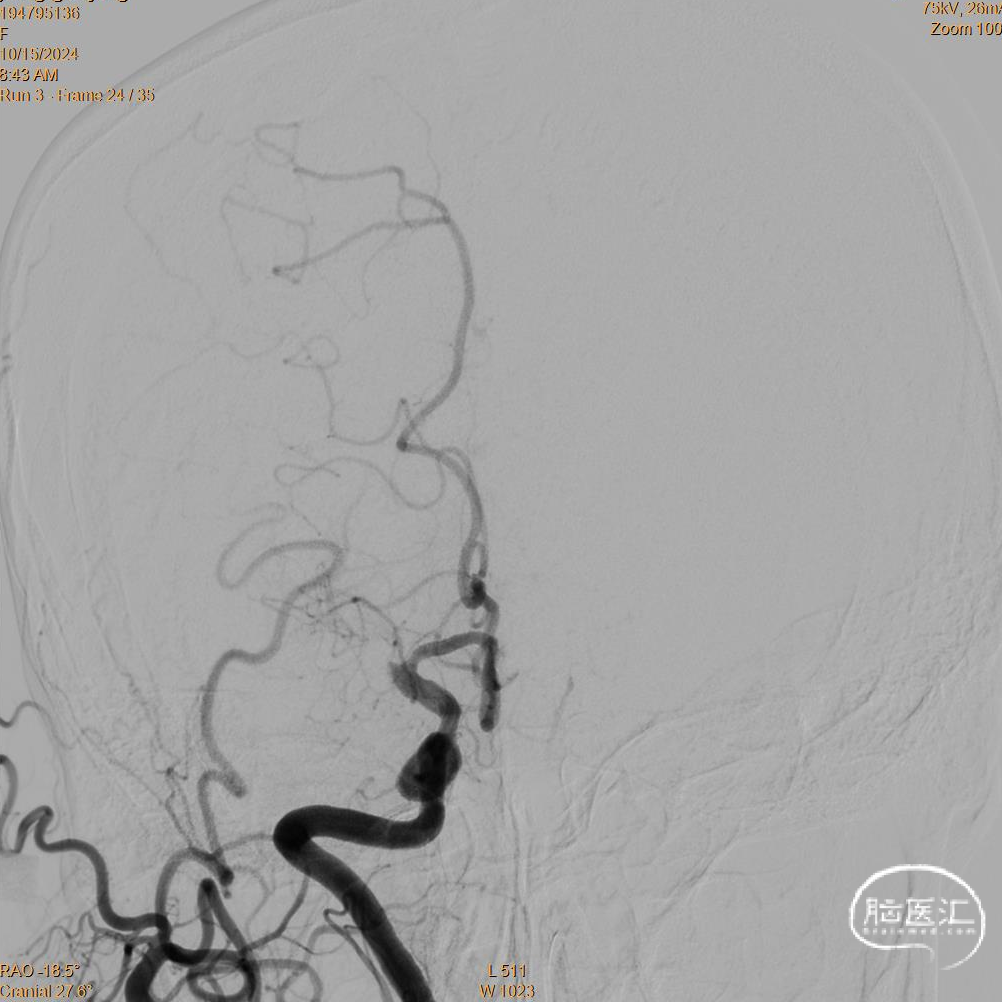

术前DSA造影

微导丝携带2.0*10mm 输送型球囊扩张微导管通过闭塞段后,冒烟提示真腔,植入4*30 通桥蛟龙®取栓支架后扩张球囊。

撤出输送型球囊扩张导管,支架释放5分钟后,8F 通桥大禹™球囊导引导管(BGC)扩张,回拉4*30 通桥蛟龙®取栓支架,6F 115 通桥银蛇®颅内支持导管与BGC共同抽吸。

卒中诊疗过程。

术后即刻复查CT,未见出血及造影剂渗出。